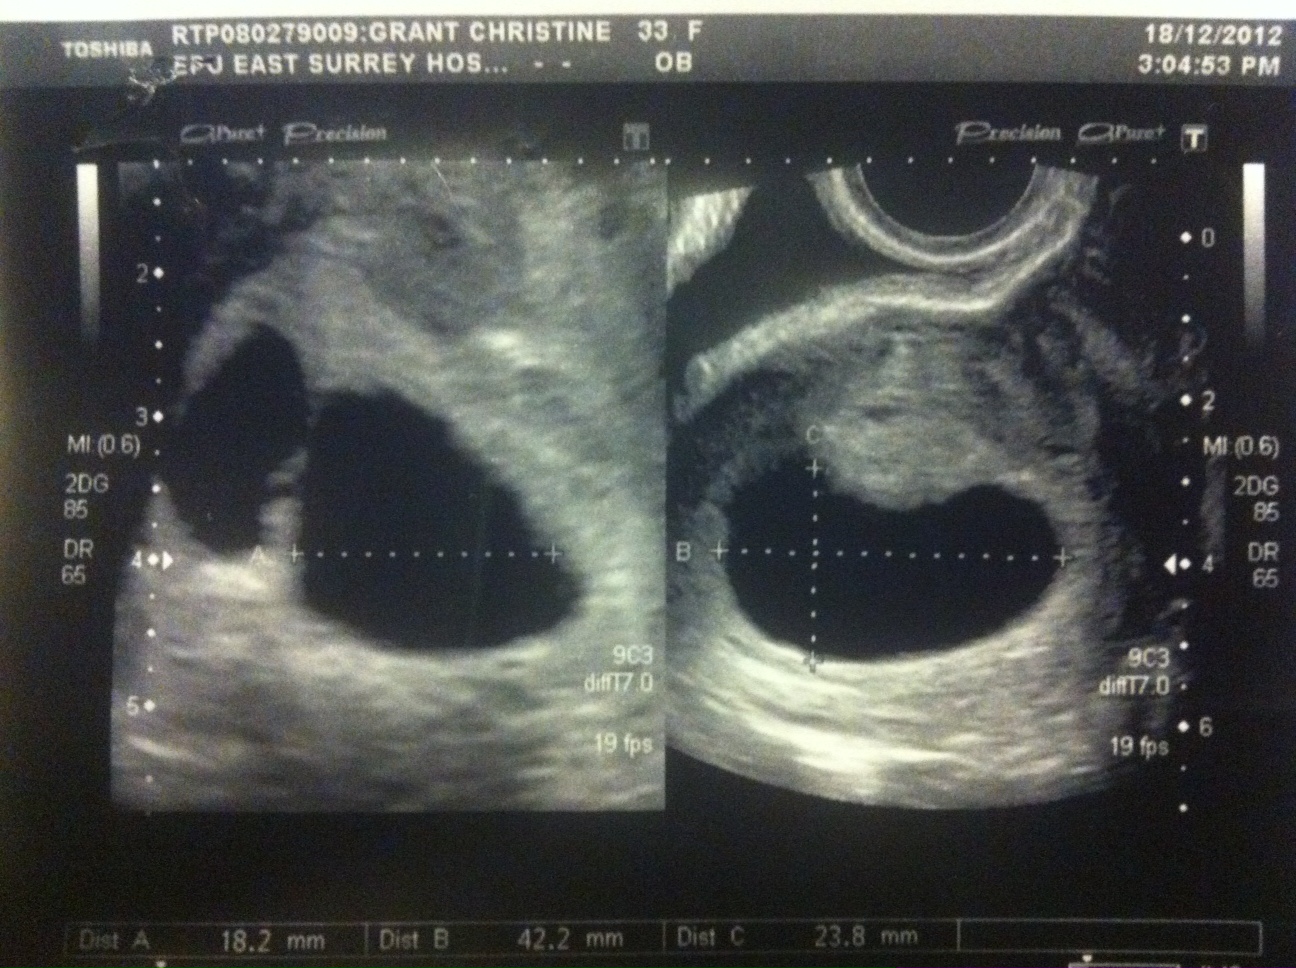

I then had a second (private) scan 6 days later and there were still 2 sacs yet this time it appeared there was a healthy baby in the big sac with yolk sac and heart beat and a CRL measurement of 13.8mm making it 7+5. The smaller sac still had an embryo and a tiny fetal pole but no heartbeat measured 3.6mm

These are the pictures I got:

Attachment 7592

Attachment 7593

Attachment 7594